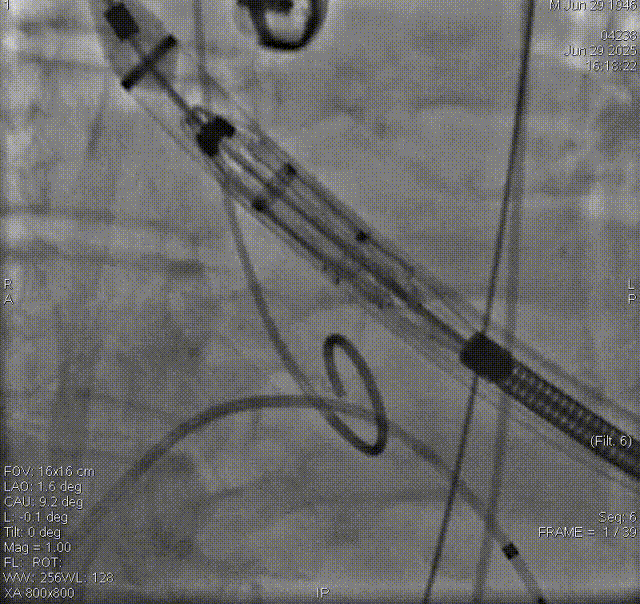

输送器经左室跨瓣

夹持件顺利入窦